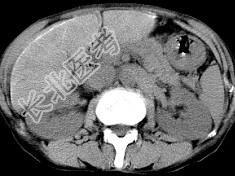

- 单项选择题男,40岁有血吸虫感染史, 腹胀不适,食欲减退, CT扫描所见如图,最可能诊断为 ( )

A、脂肪肝

B、肝炎后肝硬化

C、血吸虫后肝硬化

D、酒精性肝硬化

E、胆汁性肝硬化